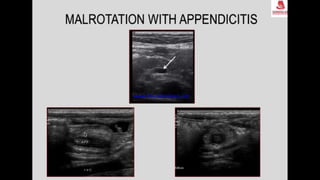

This document discusses the evaluation of right lower abdominal pain and lists appendicitis as a key cause. It notes that other potential causes include hemorrhagic cysts, heterotrophic pregnancy, salpingitis with pyosalpinx, funiculitis, and torsion of an undescended testis. The document was presented by Dr. A.S.M. Sufian of Cumilla Medical College Hospital and thanks the audience for their patience and listening.